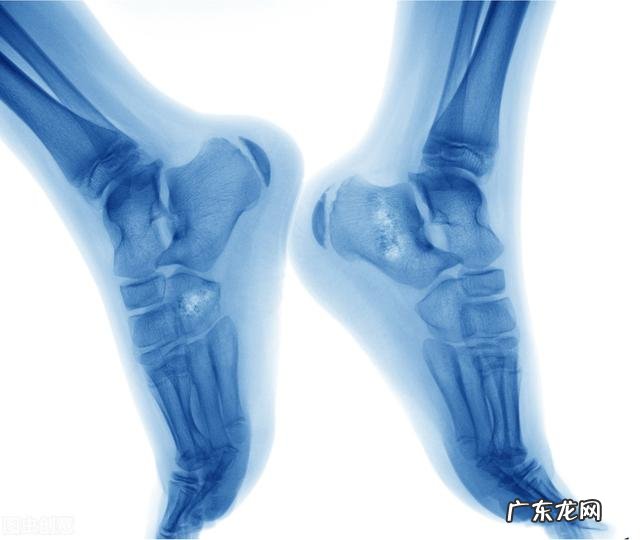

2、骨折

在大多数情况下,骨肿瘤会在上臂和腿的长骨以及骨盆中发展 。癌症会削弱存在肿瘤的骨骼,并可能导致骨折,会让人感到剧烈疼痛 。这种骨折可能发生在骨肿瘤附近或通过骨肿瘤本身发生 。